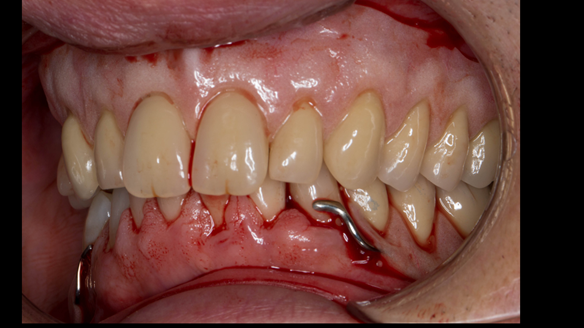

This 52 year old man was referred to me from his general dental practitioner in 2018.

10 years prior to consultation the patient's general dentist diagnosed periodontitis and referred him to Manchester Dental Hospital. He received a treatment plan to manage the periodontitis. Unfortunately, this was not acted on. Four years ago gaps developed between the upper front teeth. Orthodontic treatment was provided to align the teeth. A bonded retainer was fitted onto the upper front teeth. Approximately one year prior to consultation with me the patient noticed the teeth moving again. He consulted his orthodontist, who advised no further orthodontic treatment. One month prior to the consultation with me the upper left central incisor fell out whilst eating.

- Generalised periodontitis; stage IV grade C: currently unstable, risk factors: smoker.

- The remaining maxillary teeth had hopeless prognosis in the short term. They exhibited 80 - 100% alveolar bone loss with increased mobility (Grade 2 - 3).

- The lower right second premolar and lower left first premolar (LR5 LL4) had hopeless prognosis in the short term. They exhibited 80 - 100% alveolar bone loss with grade 3 mobility.

- The remaining mandibular teeth had approximately 30 - 50% alveolar bone loss with grade 1 mobility.

The clinical situation and treatment process is shown in detail below with photographs.